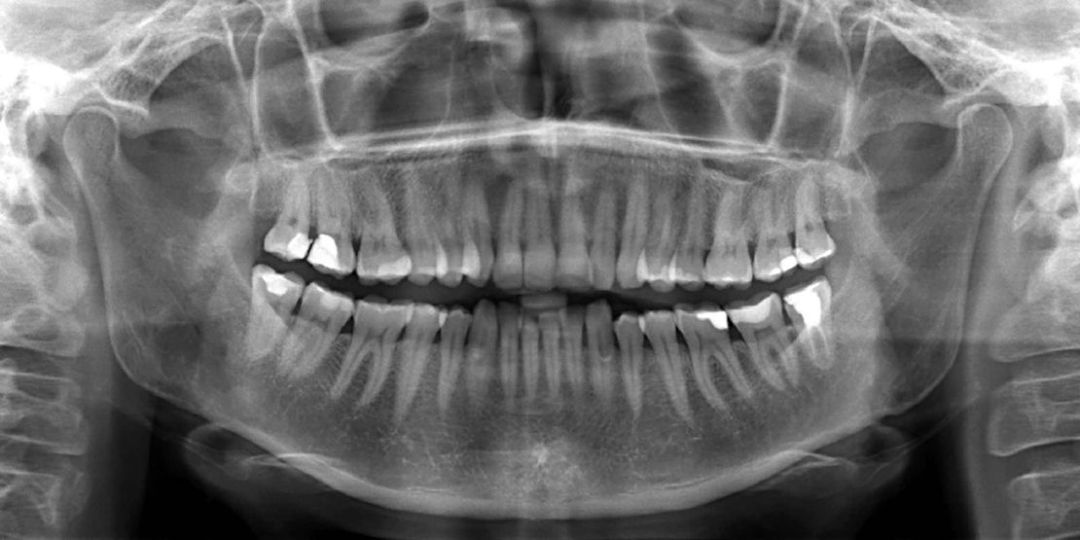

Диагностика

Врач проводит визуальный осмотр и делает прицельный рентгеновский снимок для оценки глубины поражения.